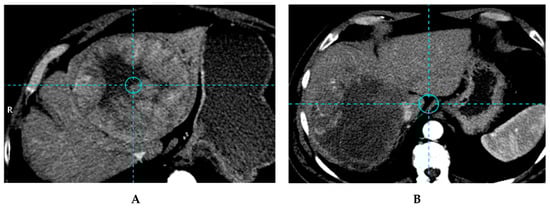

2.4.1. Segmentation

2.4.2. Specific Angiographic Requirements for a Simulation-Based Dosimetry